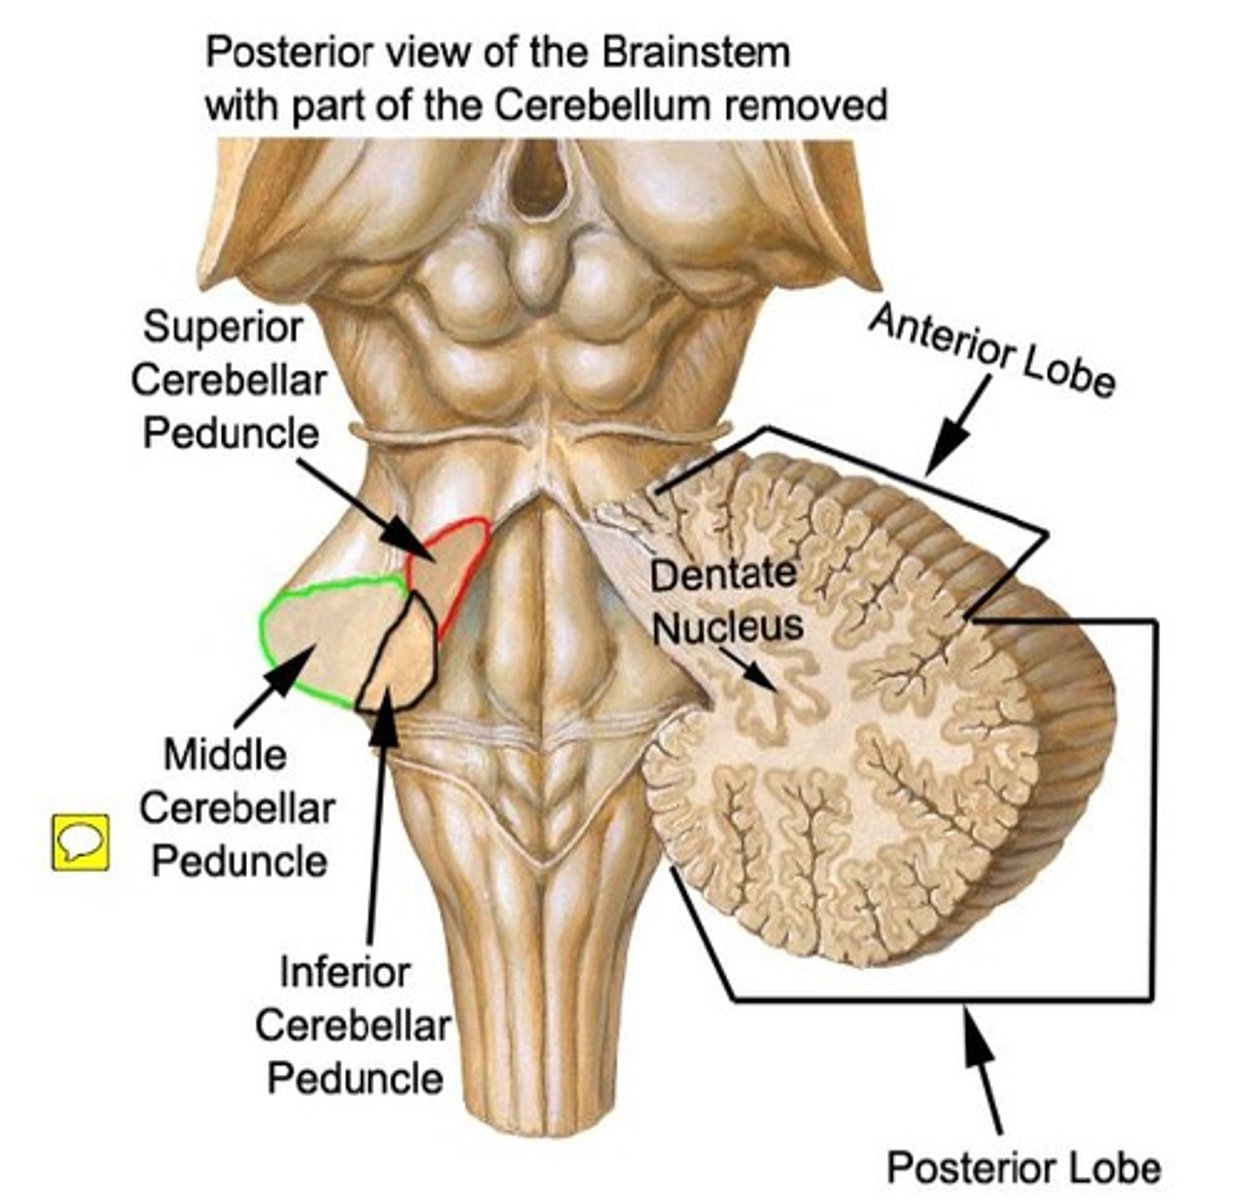

white matter stalks that connect the medulla to the cerebellum

**these help to form the lateral walls of the caudal portion of the 4th ventricle

inferior cerebellar peduncles

white matter stalks that connect the pons to the cerebellum

middle cerebellar peduncles

What forms the superior portion of the roof of the 4th ventricle? (A)

superior cerebellar peduncles